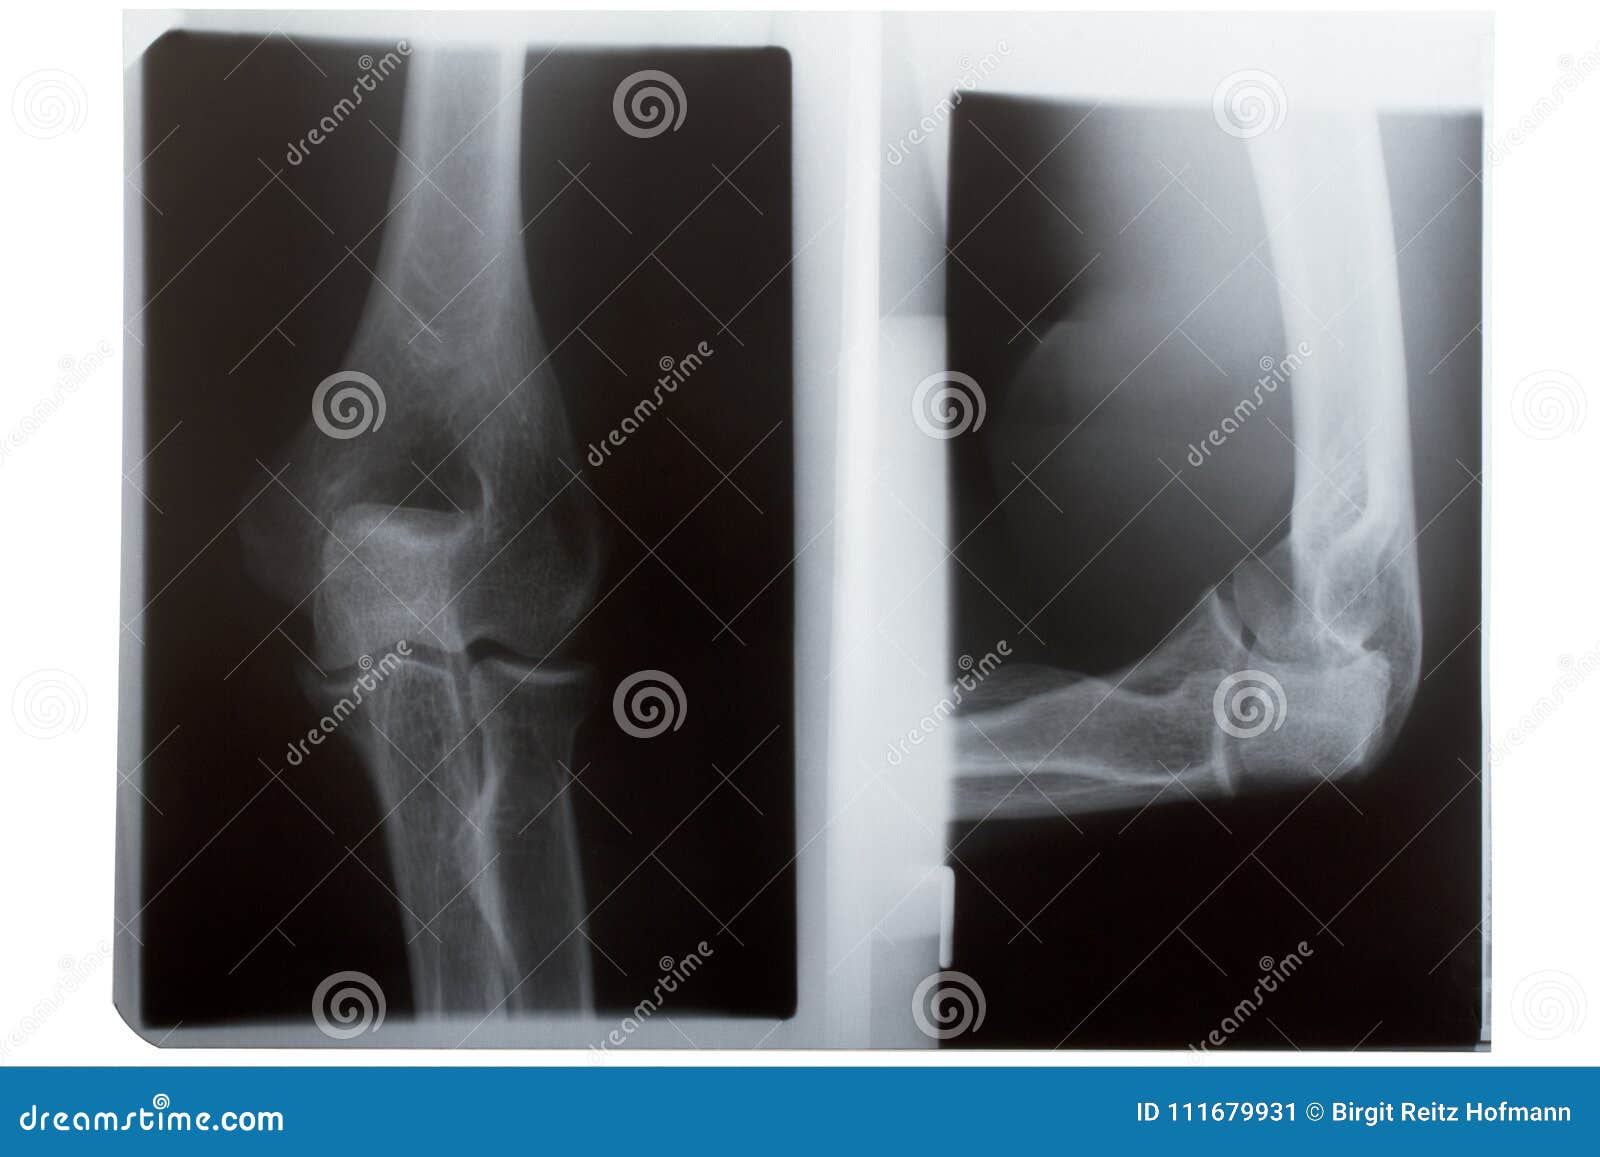

Initial plain radiographs of the right elbow. AP (2A) and Lateral (2B Right Elbow Ap The beam passes perpendicular to the elbow from anterior to posterior. The elbow series is a set of radiographs taken to investigate elbow joint pathology, often in the context of trauma. The standard anteroposterior (ap) view is obtained by placing the upper extremity adjacent to the radiographic table with the posterior surface of the extremity contacting the cassette. Anteroposterior (ap). Right Elbow Ap.

film xray elbow AP/Lateral normal human's elbow Stock Photo Alamy Right Elbow Ap The standard anteroposterior (ap) view is obtained by placing the upper extremity adjacent to the radiographic table with the posterior surface of the extremity contacting the cassette. The beam passes perpendicular to the elbow from anterior to posterior. The elbow acute flexion ap views are modified elbow ap projections for patients who cannot straighten their arm for. To identify an. Right Elbow Ap.

Radiography of Right elbow AP and Lateral position. Medical concept Right Elbow Ap The standard anteroposterior (ap) view is obtained by placing the upper extremity adjacent to the radiographic table with the posterior surface of the extremity contacting the cassette. The ap view should be. Ap (a) and lateral (b) radiographs of the right elbow showing a minimally impacted radial head fracture (teal arrows). Standard radiographic examination of the elbow includes anteroposterior (ap). Right Elbow Ap.